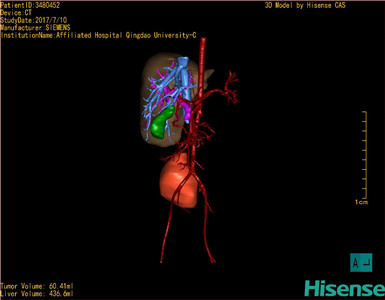

通过调节窗宽窗位调整CT序号,对肿瘤,肝实质,胆囊,下腔静脉,肿瘤,肝动脉、门静脉及肝静脉等进行三维重建;系统自动计算肿瘤体积和肝脏体积。模拟手术操作,自动计算切除肿瘤体积。肝脏体积为436.6ml,肿瘤体积为60.41ml,与血管联系紧密,术前手术方案的规划。

术前三维重建:

重建图片